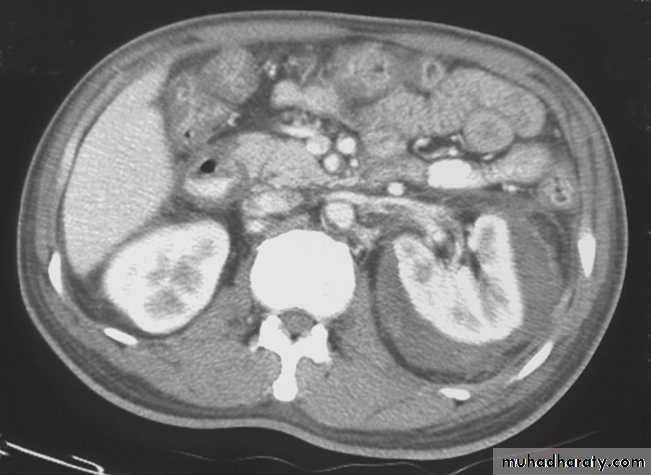

At CT:

-A typical simple renal cyst is a spherical mass with an imperceptible wall . The interior of the cyst is homogeneous with attenuation values similar to water.

-Angiomyolipomas are usually incidental findings. They are benign tumours, which rarely cause problems, although, on occasion, they cause significant retroperitoneal haemorrhage.

At CT their fat content allows a confident diagnosis (Fig. 8.32b, c).

-Renal cell carcinomas are approximately spherical and often lobulated .With density similar to renal parenchyma or slightly less with often seen some areas of necrosis & calcification .